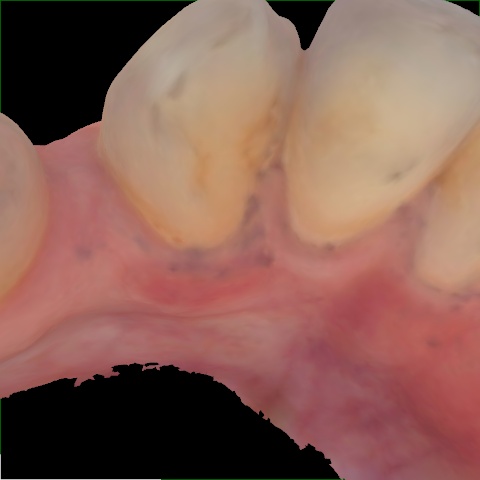

Image 318 / 400

NHD20794

Annotated as "Good"

Original Image Rendering Image